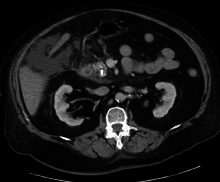

Acute exudative pancreatitis on CT scan

A contrast-enhanced CT scan is usually performed more than 48 hours after the onset of pain to evaluate for pancreatic necrosis and extrapancreatic fluid as well as predict the severity of the disease. CT scanning earlier can be falsely reassuring.